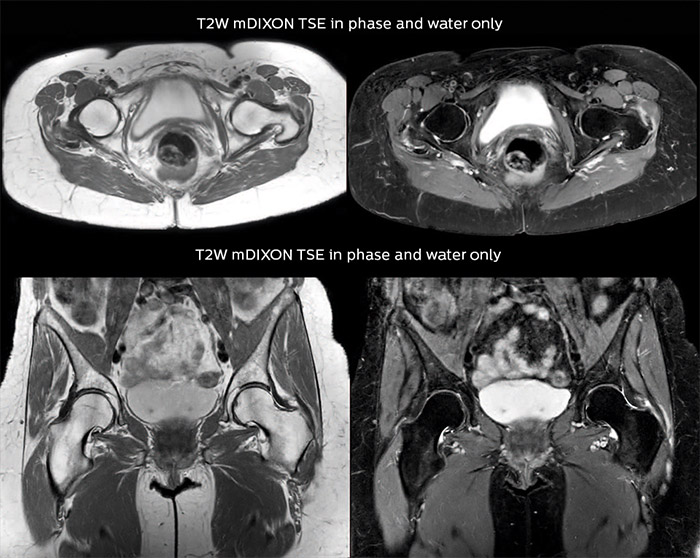

Bone assessment with confidence

“For bone assessment near joints, mDIXON TSE provides the visualization and multiple contrasts to describe abnormalities within a limited number of acquisitions. Bone marrow signal abnormalities are common MRI findings that can represent various underlying causes, from normal variance to malignancy. So, it is important for us to notice and characterize these findings. With different contrasts, both with and without fat signal as mDIXON TSE efficiently provides, we can make a confident diagnosis.”

“Other examples in bone are the signal description of a necrotic fragment in osteonecrosis, the signal description of tumoral matrix that has different components (necrosis, hemorrhage, cartilage, bone formation). These are all possible thanks to in-phase and water images from a single mDIXON acquisition.”

“In peripheral joints, mDIXON TSE imaging aids in diagnosing injuries in ligaments or tendons, for imaging degenerative and inflammatory pathologies such as osteoarthritis and rheumatologic disorders and for oncological exploration.”

“For tendon and ligament assessment around knee, ankle, hip and elbow, mDIXON TSE contributes to diagnostic confidence thanks to having images both with and without fat suppression – and without time penalty. This is possible because 2-point mDIXON is faster than the common 3-point Dixon method. It can also increase efficiency as it helps avoid having to add scans during the exam.”

“In peripheral joints, we get good image quality in difficult areas with mDIXON TSE.

Fat suppressed images appear homogeneous over the entire image, even with large coverage at 3.0T – for instance in scapular or hip girdles – or in the bearing areas or around metal prostheses, where fat suppression is often deficient with STIR or spectral fat suppression, causing diagnostic difficulties. If a diagnostic image is right the first time, we don’t need to repeat or add a sequence.”

“mDIXON TSE sequences allow simultaneous characterization of morphological changes from the in-phase T2-weighted images and visualization of edematous changes, thanks to the water T2-weighted images from the same acquisition. Anatomical and morphological considerations could be a partial or complete ligament tear, a bony avulsion or hematoma.”